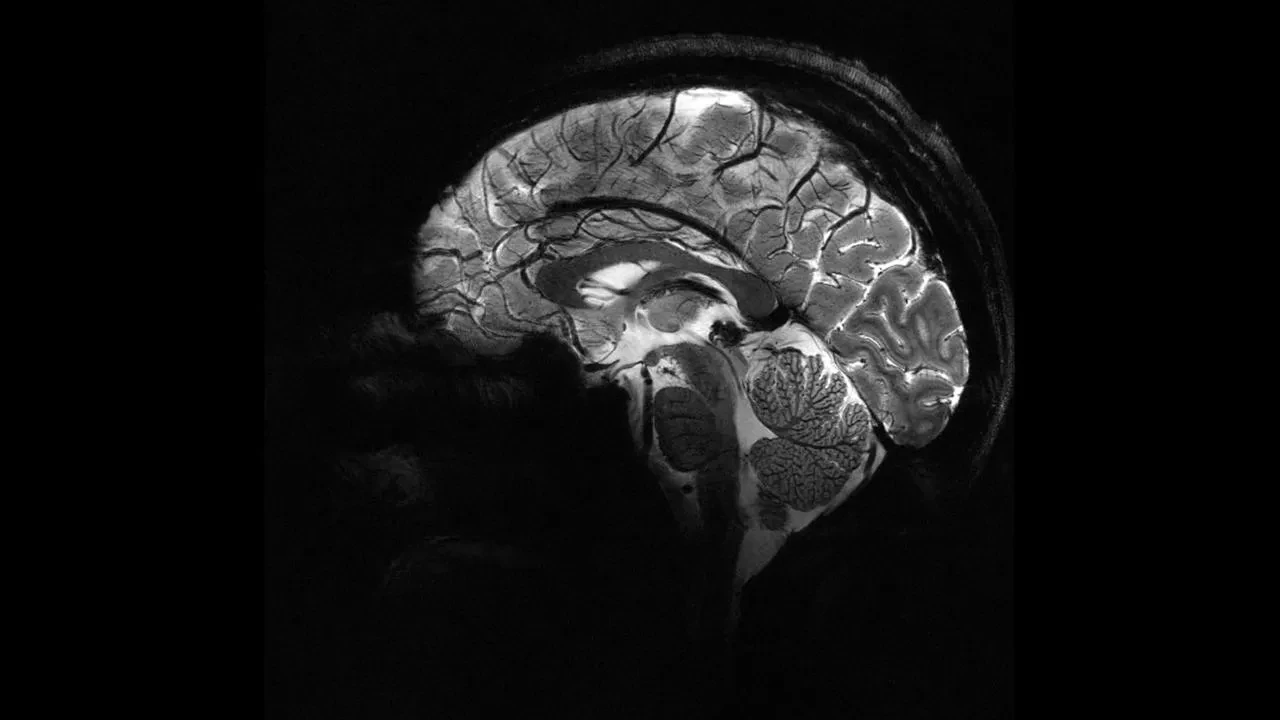

Nottingham Üniversitesi’nden bilim insanları, UK Biobank’ta yer alan 15 binden fazla yetişkinin verileriyle sağlıklı beyin yaşlanmasını tanıyan bir yapay zekâ modeli geliştirdi. Model, pandemiden önce tarananlarla, önce ve pandemi sırasında taranan iki grubun beyin yaşlarını karşılaştırdı.

Araştırmaya göre, pandemi sürecinde insan beyninin yaşlanma hızı ortalama 5,5 ay öne çekildi.